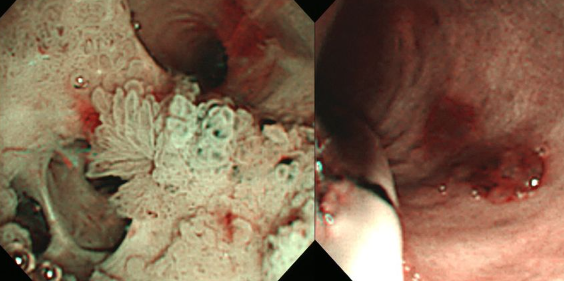

- ERCP 시술을 통해 막힌 담관을 열어주는 시술이 선행되며, 이후 치료가 진행됩니다.